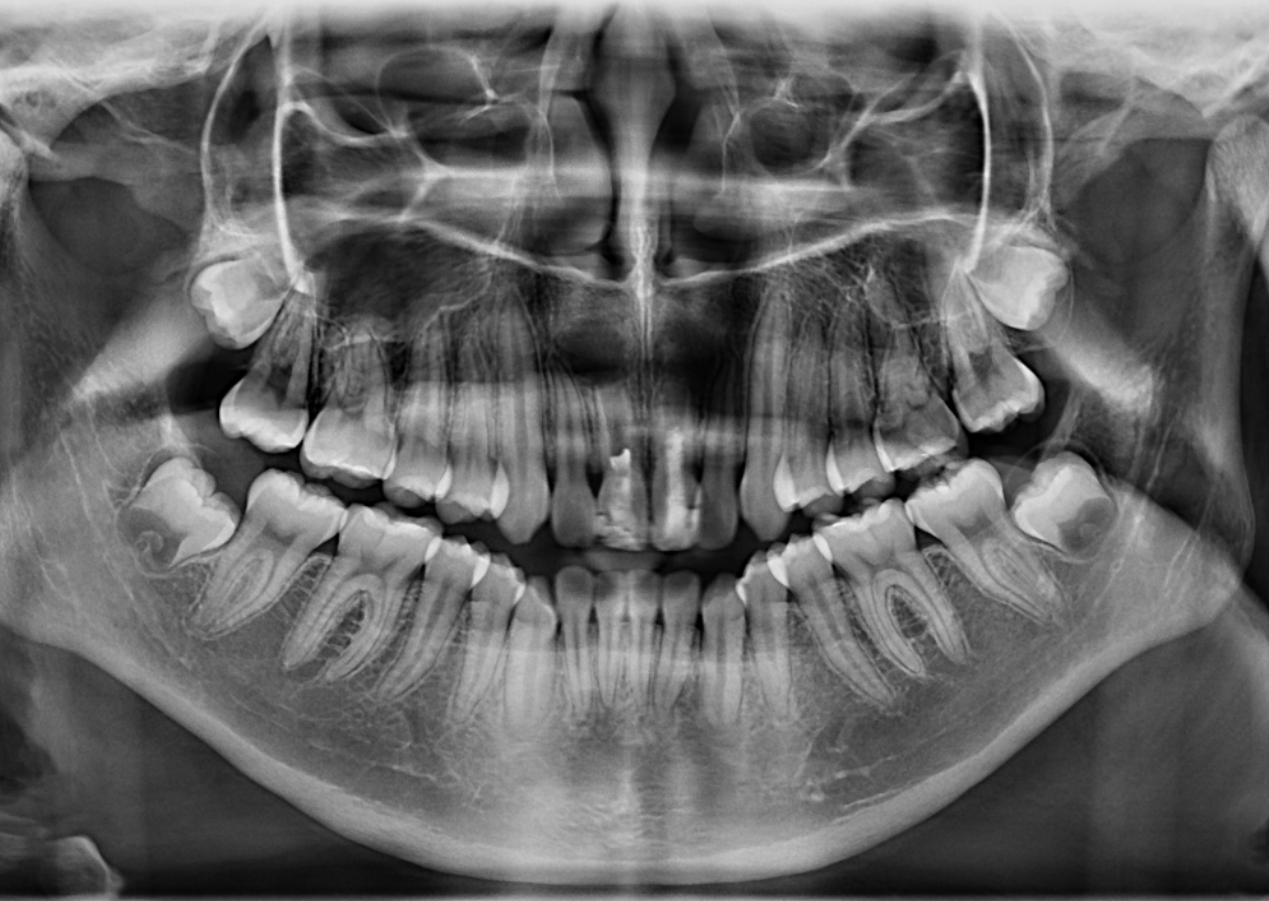

En la radiografía panorámica (Figura 1) se observan las piezas 11 y 21 con disminución de la longitud radicular, conductos radiculares amplios y ápices abiertos. Asimismo, se evidencia material restaurador coronario desadaptado, obturación endodóntica parcial y la presencia de un proceso osteolítico periapical difuso.

RADIOGRAFÍA PANORÁMICA